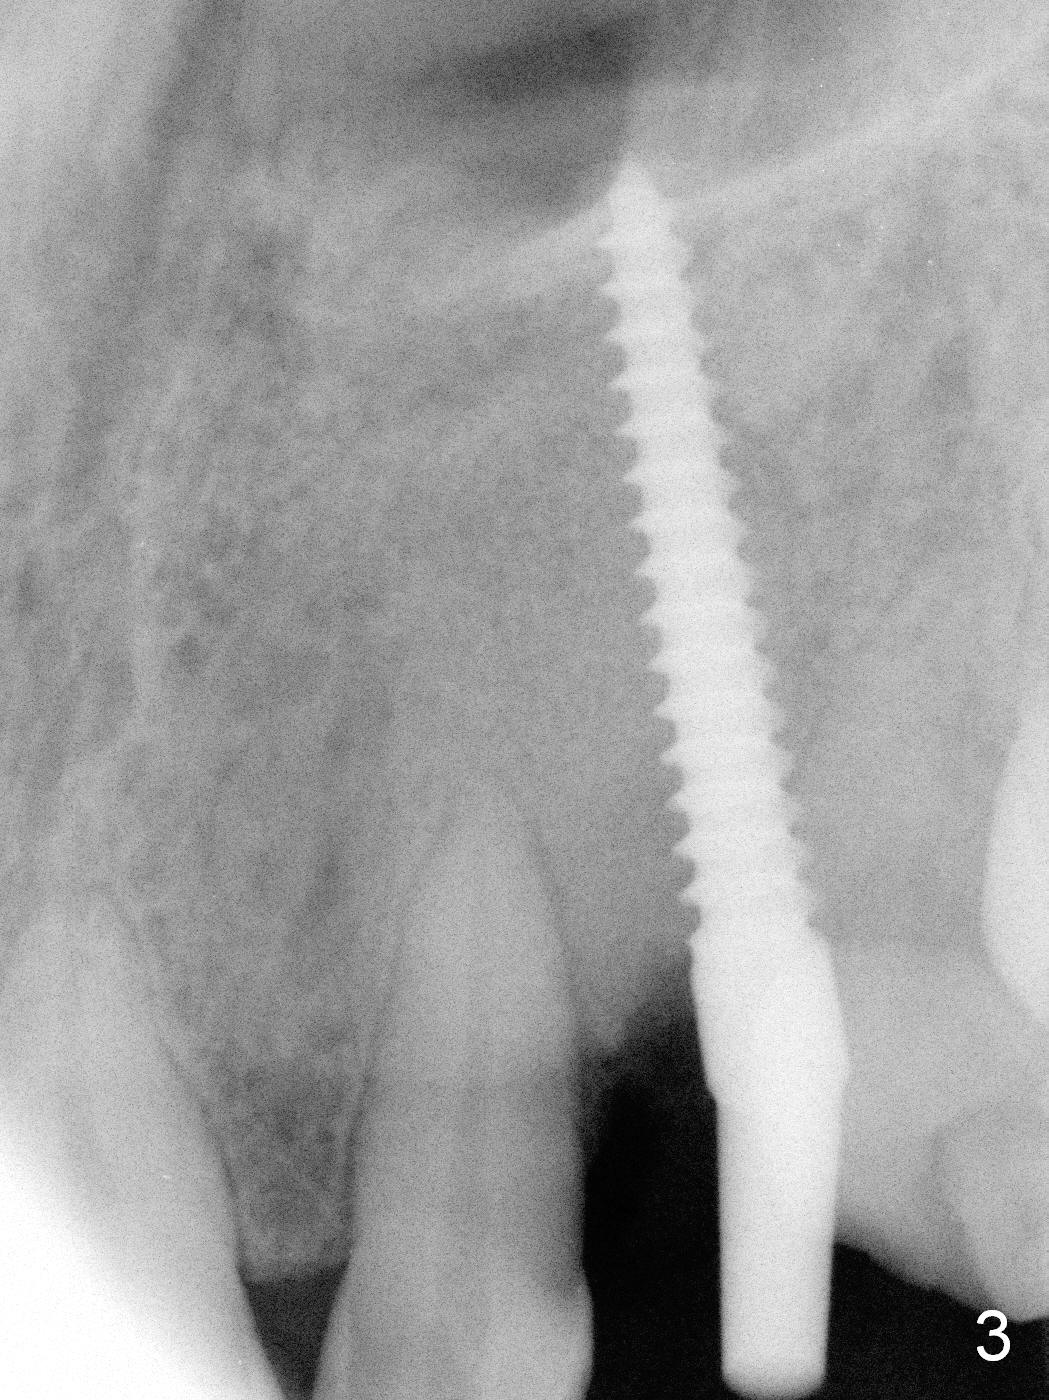

The ridge looks wide clinically 4 months post implant removal and socket preservation. In fact, the graft bone is soft and the ridge is narrow after incision. It appears that an angled 1 piece implant is an indication. A 1.2 mm pilot drill is used to start osteotomy. At approximately 17 mm, the patient feels pain. The nasal floor perforates? A 2 mm osteotome is utilized to enlarge the osteotomy. At 17 mm, the osteotome is stable (Fig.1), but the nasal floor appears out of view. Review of the preop PA shows that the distance between the gingival margin and the nasal floor (arrowheads) is ~22 mm (Fig.2). It should be safe and necessary to place a 3x20 mm 1-piece implant with 15° angulation. Insertion torque is between 40 and 45 Ncm.

Intraop PA shows that the nasal floor is perforated (Fig.3). The patient experiences bilateral nasal obstruction. Sneezing produces trace of hemorrhage from the left nostril and large amount of secretion from both nostrils. The nasal speculum is misplaced in the clinic. Clinical nasal floor perforation cannot be confirmed. After abutment preparation, an immediate provisional is fabricated. Afrin is prescribed. Post-op instruction includes continuing Amoxicillin and Chlorhexidine rinse. A few hours postop, the patient reports no abnormality.

Eight months postop, the patient returns for #11 restoration. She reports no problem at #11, while there is light tenderness with a 2-piece implant (4.5x20 mm) at #6 at night (Fig.10, a portion of panoramic X-ray). Clinical exam reveals no abnormality at #6. Although the implant at #11 is buccally placed, there is no buccal plate atrophy (Fig.6,7). In fact the 20 mm 1-piece implant is placed in the bone (septum) between the nasal cavity (Fig.10 pink dashed line; Fig.13 (CBCT (52 year-old lady) N) and the maxillary sinus (yellow dashed line, S). In fact the apparent nasal floor indicated as arrowheads in Fig.2 and 10 is the horizontal plate of the palatine bone (hard palate)! Therefore there is no nasal floor perforation in this case. A long implant is indicated in the upper canine.